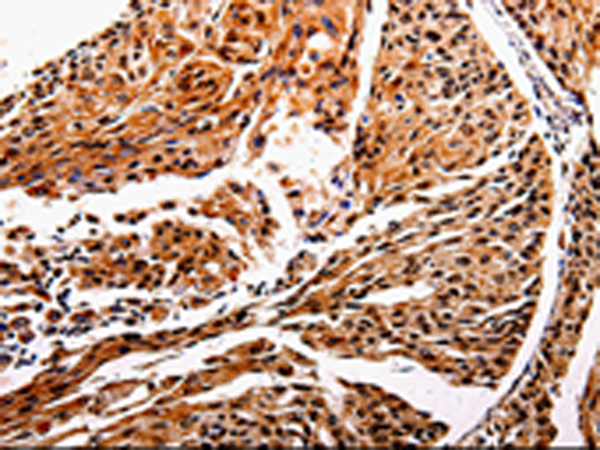

IHC positive control: |

Human cervical cancer and human esophagus cancer |